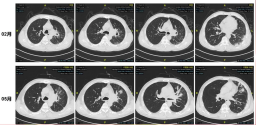

由于左肺病灶侵犯肺动脉,肺内及肝内有转移瘤,肺癌暂无手术指征。同时,因合并曲霉感染及肠癌,全程抗肿瘤化疗存在困难。因此抗曲霉治疗需先行:伏立康唑静脉治疗后序贯口服;全身抗肿瘤方案需温和且兼顾:曲霉感染控制后选择行紫杉醇+奥沙利铂+替吉奥抗肿瘤治疗。

治疗过程中,定期监测伏立康唑血药浓度,确保在正常范围,期间基因检测未见突变。

患者自行停用伏立康唑口服治疗后,曲霉感染复发,左肺肺不张病灶逐渐增大。再次评估后,继续给予伏立康唑静滴抗曲霉治疗,并停用免疫治疗,改为单药化疗联合抗血管生成治疗,使用安罗替尼。